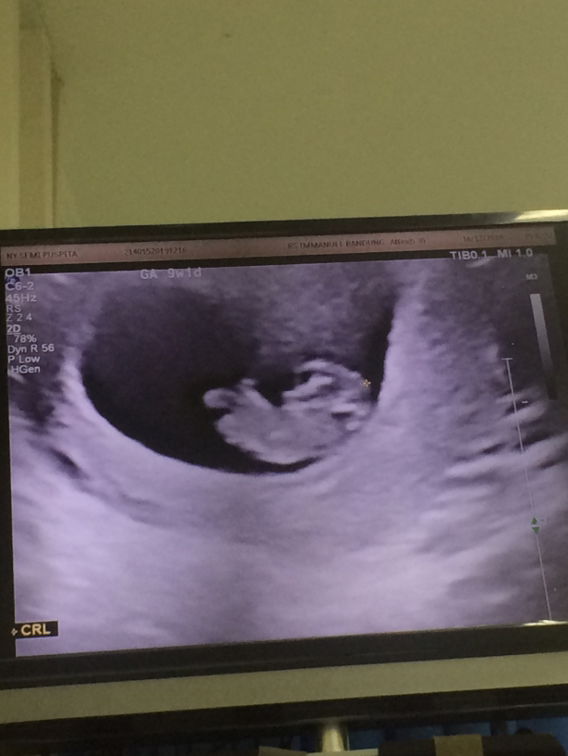

Assalamualaikum, Bunda Sharing dong. Kemarin Saya Habis Kontrol usia kandungan 9w1d. Alhamdulillah Sudah Semakin Tumbuh kata dokter di jelasin ini kepala, ini tubuh dan kaki.

Alhamdulillah Sudah Terdeteksi Detak Jantung nya. Lalu Saya bandingkan dengan di aplikasi. Kalau di aplikasi udh berbentuk jelas kepalanya. Menurut Bunda Apakah Normal?